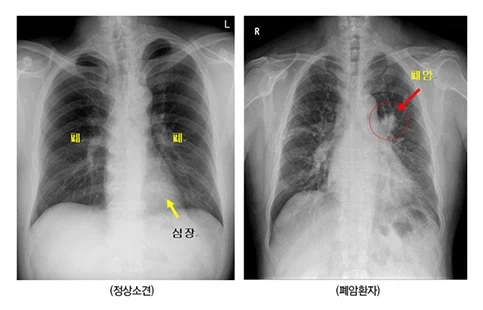

의외로 남자들이 무서워하는 엑스레이 사진.jpg Anonymous | 2026.03.30 05:10 | 조회 10 https://qquing.net/bbs/board.php?bo_table=humor&wr_id=1873572 주소 복사 이전글 다음글 랜덤 만화 목록 본문 ㅈㄹ 무서움 추천 0 비추천 0